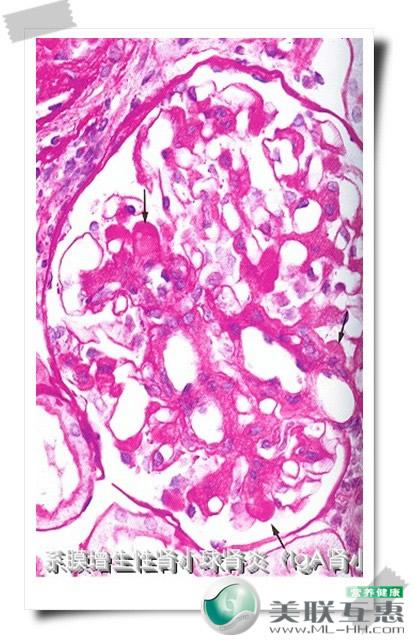

IgA肾炎